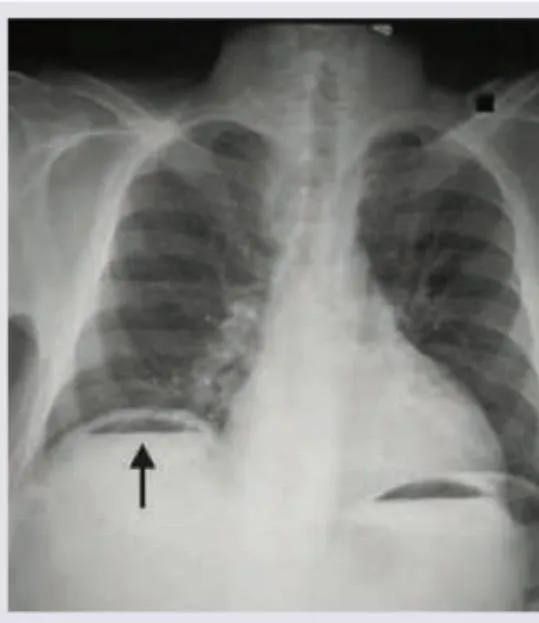

- Erect CXR: detects 70-80% of perforations (free gas under diaphragm)

⚠️ Warning: Up to 30% of perforations have no free gas on CXR - CT is gold standard if clinical suspicion persists

✓ Imaging hierarchy: Erect CXR (70-80% sensitive) → CT with contrast (>95% sensitive, shows site/cause)

✓ 30% have no free gas on CXR - don't exclude perforation without CT if clinical suspicion remains